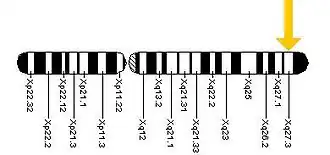

- Дисфункция отдельных генов. Число генов, мутации в которых вызывают ту или иную степень умственной отсталости, превышает 1000. В их число входят, например, ген NLGN4, находящийся на хромосоме Х, мутации в котором обнаружены у некоторых пациентов, страдающих аутизмом; ген FMR1, сцепленный с хромосомой Х, дерегуляция экспрессии которого вызывает синдром хрупкой Х-хромосомы; ген MECP2, также находящийся на хромосоме Х, мутации в котором вызывают синдром Ретта у девочек[18].